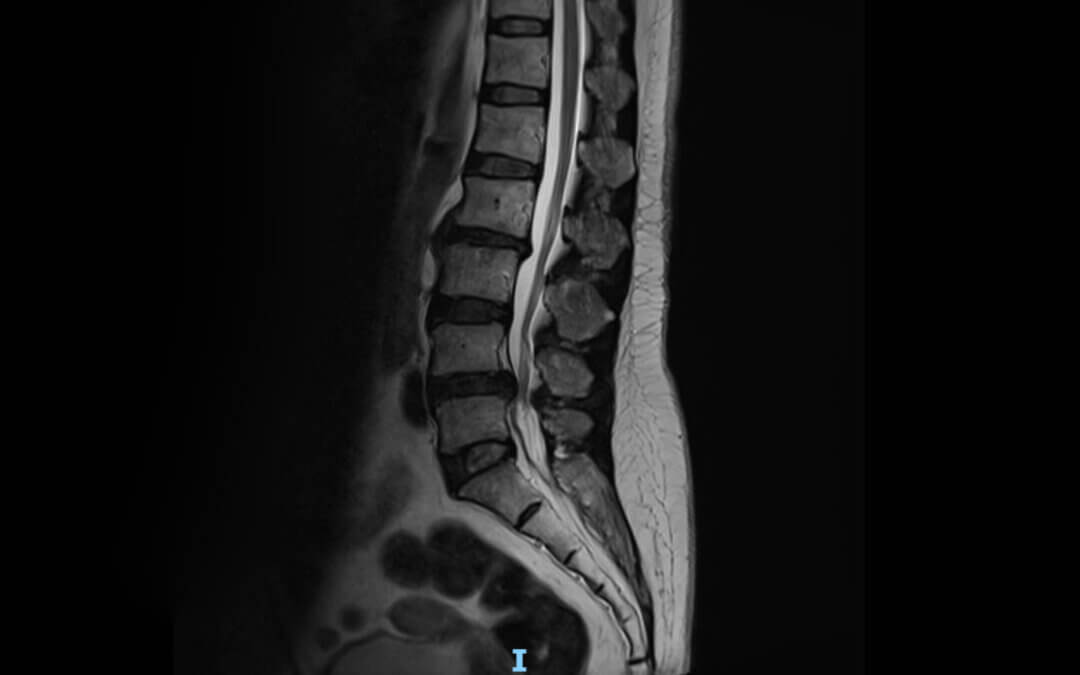

An MRI is Critical Before Spinal Decompression

by Dr. Darrell Swolensky | Mar 5, 2026 | Uncategorized

Why an MRI is Critical Before Non-Surgical Spinal Decompression The Essential First Step for Safe and Effective Disc Treatment Introduction If you are considering non-surgical spinal decompression, one of the most important steps before beginning treatment is...